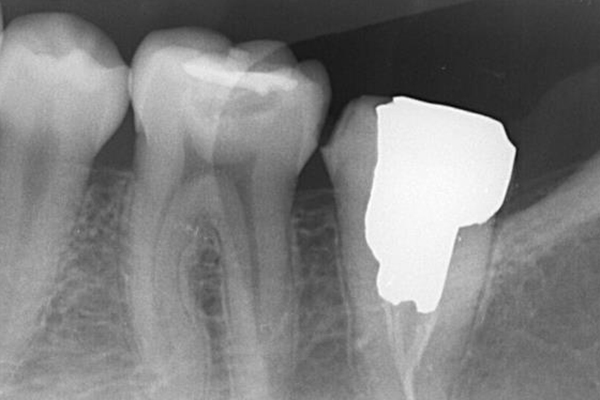

2.初診時エックス線写真

左上の1番奥の歯はすでに神経がとってあり、

大きなむし歯を認め根分岐部の歯周ポケットは8mmでした。

今回の症例では、歯根の途中にパーフォレーション(穴があいている)が認められ(黄矢印)、根の間の骨(青丸)が溶けていました(根分岐部病変)。

3.CT撮影

根管治療は小さいCTを撮影することで、より精密な治療が可能となります。本症例ではパーフォレーションによる根分岐部病変と根尖病変が併発しているという診断になりました。